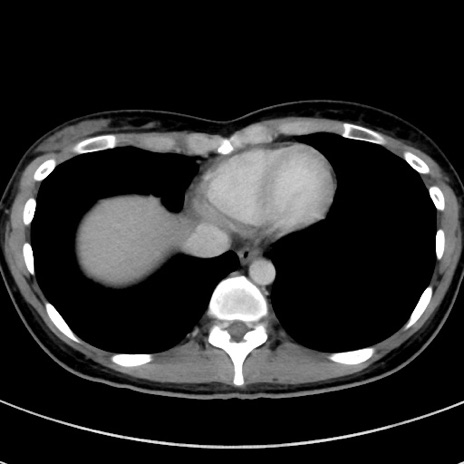

冠状断像